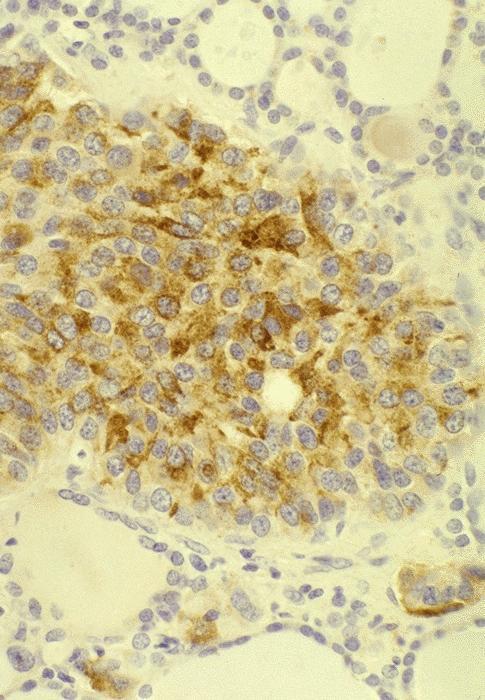

Microscopic (histologic) description

- Wide variety of morphology, can mimic any other thyroid malignancy

- Round, plasmacytoid, polygonal or spindle cells in nests, cords or follicles; often mixtures of these cells

- Round nuclei with finely stippled to coarsely clumped chromatin and indistinct nucleoli, occasional nuclear pseudoinclusion

- Eosinophilic to amphophilic granular cytoplasm due to secretory granules

- Generally low mitotic figures

- Stroma has amyloid deposits from calcitonin, prominent vascularity with glomeruloid configuration or long cords of vessels (Am J Surg Pathol 1995;19:642), coarse calcifications, occasional psammoma-like bodies

- Mucin in 42% (Arch Pathol Lab Med 1983;107:70)

- Often angiolymphatic invasion

- Occasionally marked neutrophilic infiltrate, oncocytic tumor cells, papillary patterns

- May entrap follicles

- C cell hyperplasia present in familial but not sporadic cases

Microscopic (histologic) images

Contributed by Shuanzeng Wei, M.D., Ph.D., Joseph Christopher Castillo, M.D. and Mark R. Wick, M.D.